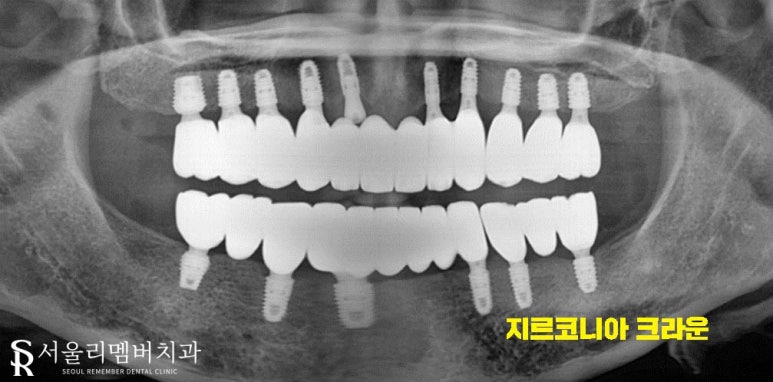

따라서 몇 차례에 걸쳐 인공치근의 역할을 해줄 임플란트 픽스처를 심었습니다.

이후, 서울대입구역 치과 에서는 지르코니아 재료를 사용해 크라운 제작을 도왔는데요.

자연치의 형태와 유사할 수 있도록 쉐이드, 색조 선택에 심혈을 가했답니다^^

하얗고 고른 이도 좋지만 제일 좋은 건 자연치처럼 티가 나지 않는 거겠죠?

주변 조직, 잇몸, 안모, 미소, 분위기 등 여러 형태를 고려하여 제작했습니다.

제작이 완료된 후에는 따로 불편한 게 없는지 재차 확인을 한 뒤에 최종 결합 도와드렸습니다.

어떤가요? 미소를 띠고 있는 사진을 보면 보철인 게 티가 안날 정도로 자연스러운 모습이네요ㅎㅎ

전체 식립으로 치료 기간이 짧진 않았으나 환자의 높은 협조도로 인해 예상했던 기간에서 크게 벗어나지 않고 마무리할 수 있었습니다.

오래도록 보철을 유지할 수 있도록 지속적인 사후관리를 약속드렸습니다.